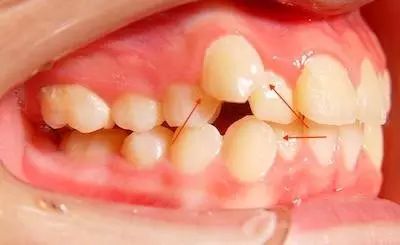

2/ 牙齿因为错位或扭转造成了牙齿之间的间隙。

5/ 智齿萌出的方向不正常,也会造成食物易嵌塞在倾斜的空隙里。